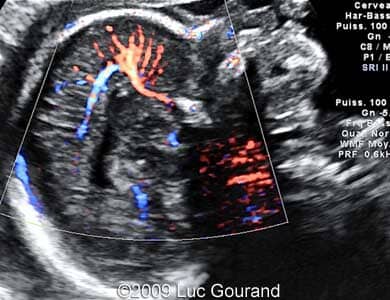

Images 5,6: Images show a Doppler imaging at 23 weeks.

Images 5,6: Doppler imaging of the mid-sagittal plane, the "pericallosal artery" has an unusual distribution, the wavy hypoechogenic structure in the position of the corpus callosum which is absent, is marked by *.

Case262_3

Case262_4